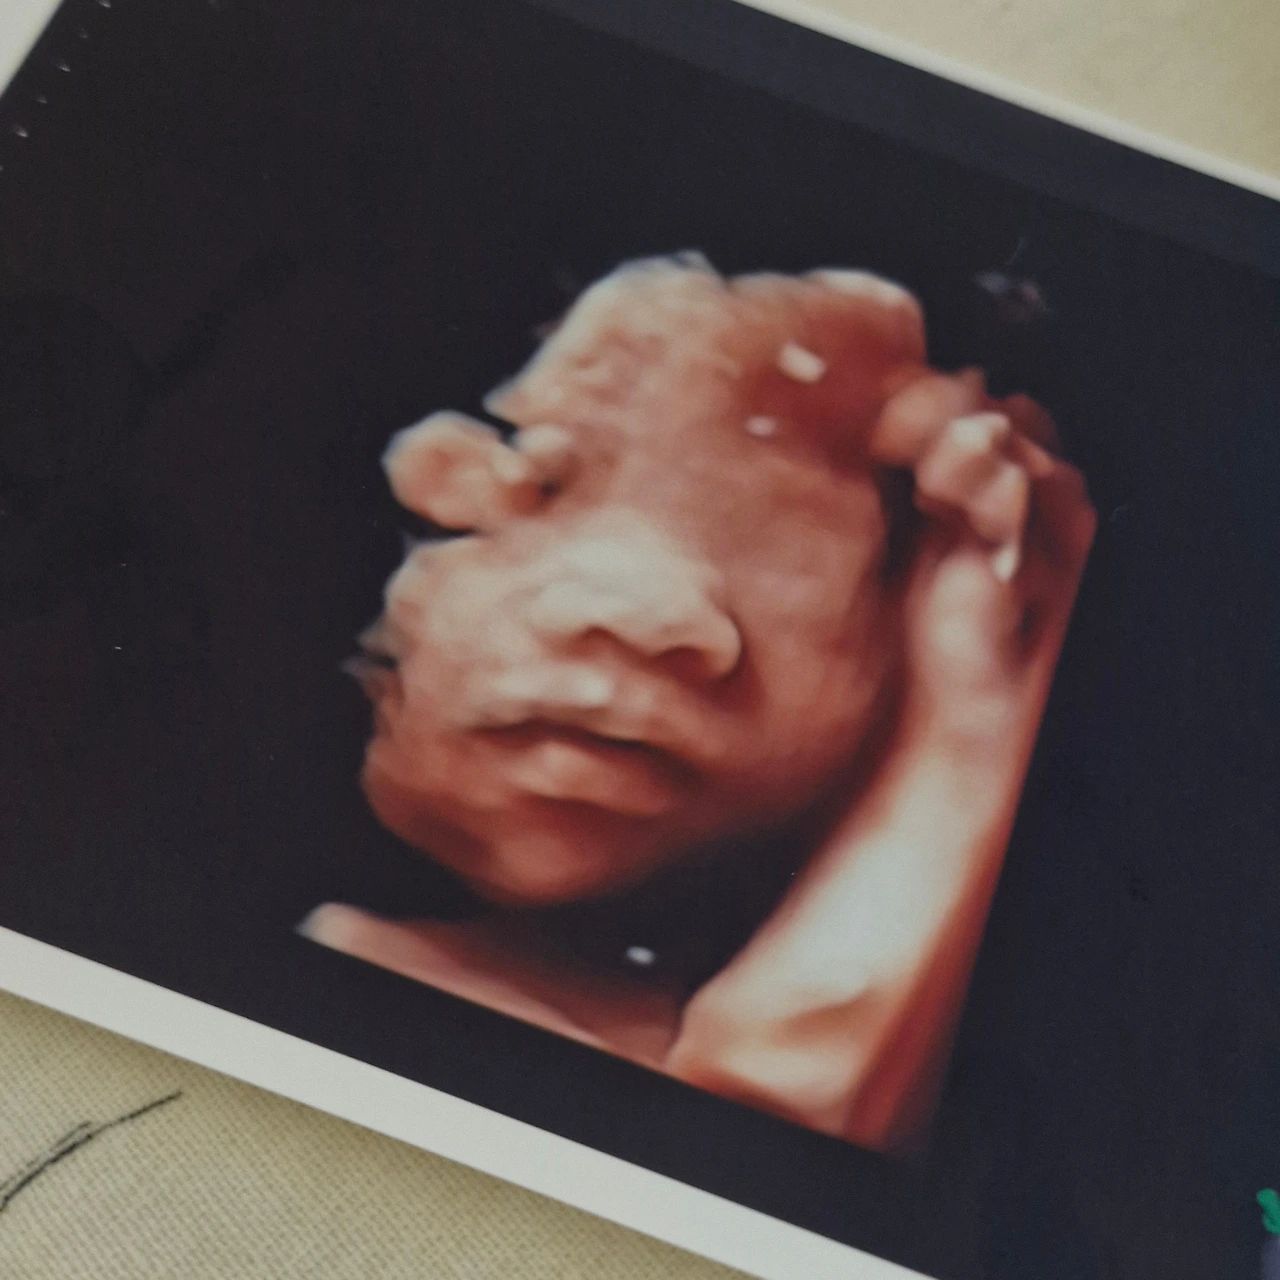

정기검진일에 무사히 주수에 맞게 자라있는 아기의 초음파 사진을 바라보면 또다시 하루를 버틸 힘이 생겼다.

내 몸을 빌려 자라는 이 작은 생명이

지금 이 모든 수고의 이유였다.